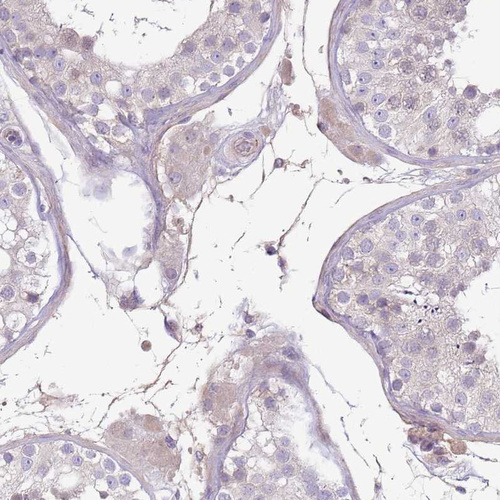

Immunohistochemical staining of human rectum shows strong positivity in plasma.